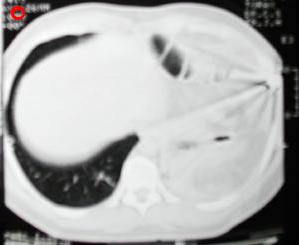

Tomografía Computarizada Tórax

Tomografía de ½ inferior del tórax y abdomen superior con contraste oral, se aprecia desplazamiento del fundus gastrico hacia la base pulmonar izquierda, la grasa epiploica, la brecha diafragmatica, tambien el proyectil y esquirlas metalicas.